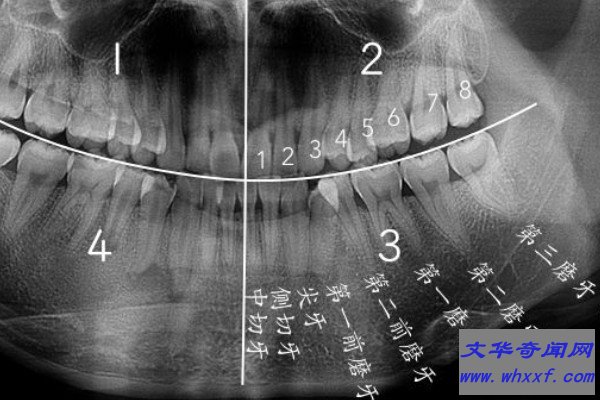

智齿是人类口腔内牙槽骨上最里面的第三颗磨牙,由于它经常会产生疼痛感,很多人选择将其拔掉,但部分人表示拔智齿后悔死了,那么这是为什么呢?快和小编去看看吧。

人在成年之后一般都会长智齿,在其生长期间可能会出现牙龈肿痛的情况,严重影响人们的日常生活,所以很多医生都建议将其拔掉,但总有人会因为拔掉后出现的不良反应而后悔。事实上,智齿对人的危害没有那么大,如果其生长状态比较良好,则没有强行拔除的必要,除非是畸形智齿。